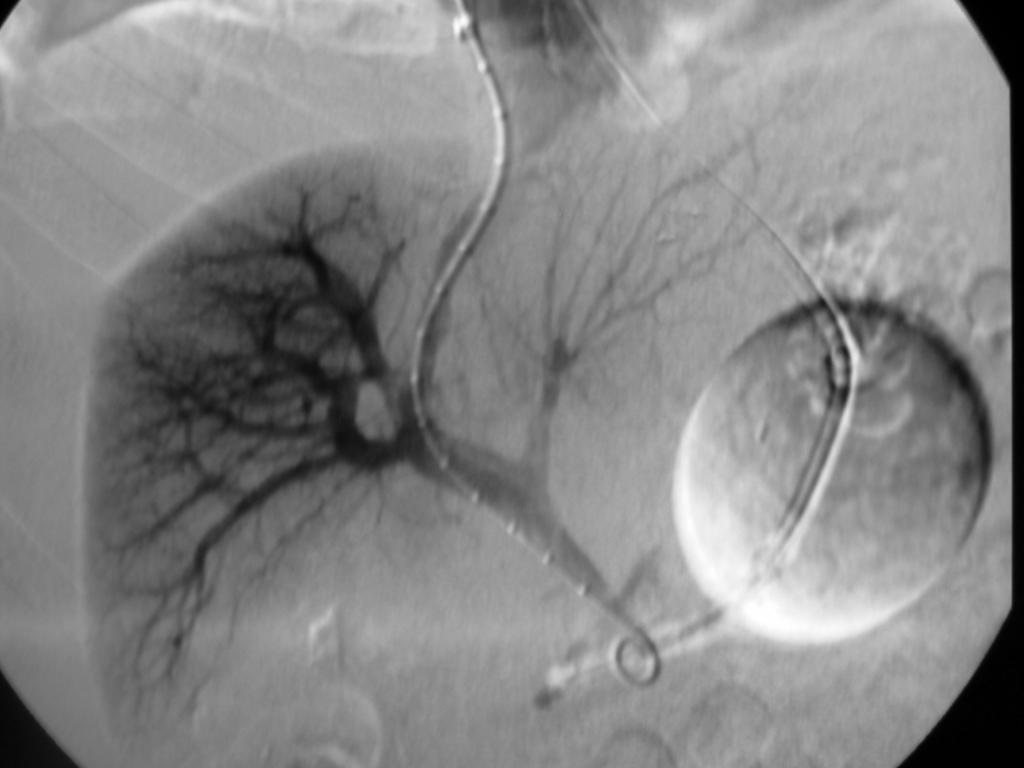

病例2:经左肝静脉-左门静脉穿刺,支撑架植入术

肠系膜上静脉血栓TIPS